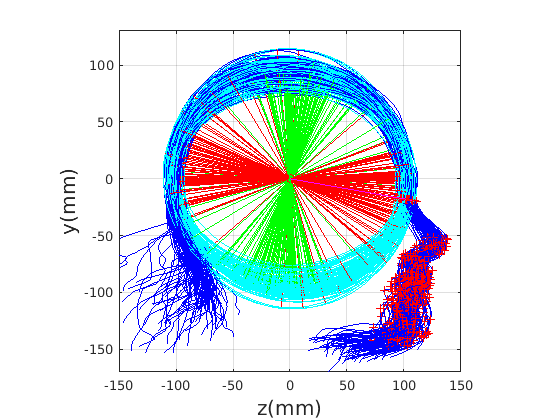

Figure 17 shows all 100 profiles overlaid with the same alignment scheme. The median value of major ellipse axis and the ellipse centre-nasion angle differ by 3.6 degrees, so that when the nasion angle is fixed at -10 degrees, the median ellipse angle is -6.4 degrees (cf. -7.4 degrees with manual landmarking of the nasion). We noted regularity in the orientation of the fitted ellipse as is indicated by the clustering of the major (red) and minor (green) axes in Fig. 17 and the histogram of ellipse orientations in Fig. 18. For most people, the major axis of the ellipse is closely aligned with the y-axis (upright), and titled slightly forwards. A minority of heads (9%) in the training sample have their major ellipse axes closer to the vertical (these relatively tall and short heads are known as brachycephalic.) Ellipse axis clustering (relative to the fixed ellipse centre-nasion line) does not appear to be sharply defined. This is because many crania are close to circular in cross-section, making the orientation of these angles sensitive to small changes in shape from one person to the next. Note also the variation at the back of the head due to a variety of hair styles, some of which protrude from under the cap. We limit the region over which we model the cranial shape in order to crop this unwanted data out.